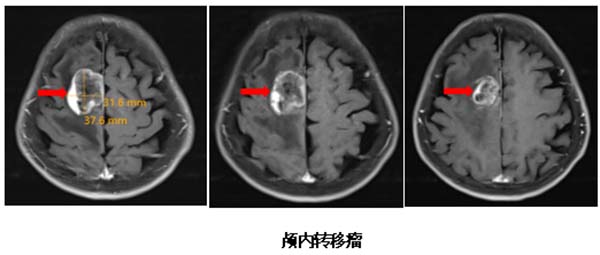

检查结果揭示了她病情急转直下的原因:头部MRI显示右侧额叶运动前区皮层转移灶,伴有明显脑水肿,严重压迫运动功能区。更复杂的是,胸部CT发现了右肺占位病变。高龄、病情进展迅速、肺部原发病变,使这个病例充满挑战。